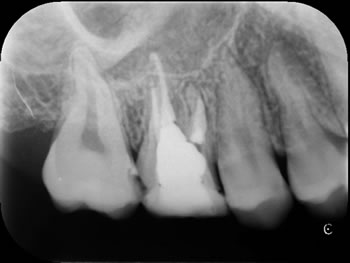

根管治療のレントゲン診査は2枚のレントゲン撮影(2方向)が必要です。

(1)では3根しか写っていません。

(2)根の本数が4本あることがわかります。角度をかえることで、病巣の大きさや、根の彎曲など様々な情報が可能になります。

(1)正方線撮影 真正面からのレントゲン

(2)偏心撮影 角度をつけたレントゲン

根の本数は4本であることがわかります。白い薬が4つ見えますね。